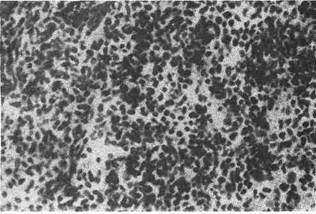

6. Мелко клеточный рак — форма недифференцированного рака, ко-

торый состоит из мономорфных лимфоцитоподобных клеток, не образующих

каких-либо структур; строма крайне скудная (рис. 142). В опухоли много ми-

тозов.Часты некротические изменения. Рост быстрый, метастазы возникают

рано. В некоторых случаях установить гистогенез- не представляется воз-

можным, тогда говорят о неклассифицируемой опухоли.